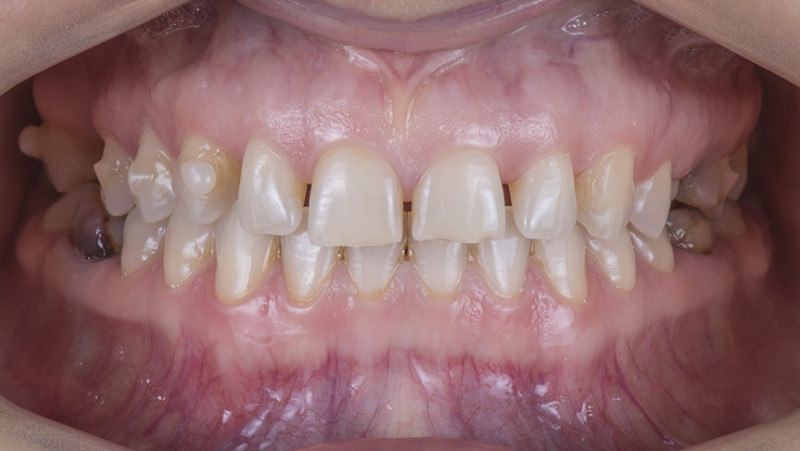

Установка керамической коронки

Изготовили и установили 22 керамические коронки EMAX и 6 виниров на нижнюю челюсть. Провели пластику десны в области 22 зуба. Устранили сильную рецессию десны в области имплантата, установленного в другой клинике.